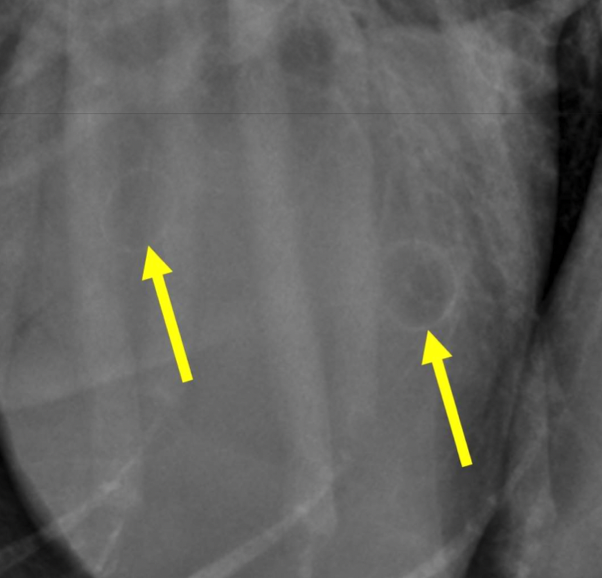

what type of pattern

right caudal lobe: intersitial- can still see vessels

left caudal lobe- alveolar- can not see vessels, can see air bronchiogram

cardiogenic pulmonary edema

left sided cardiomegaly- left auricular bulge